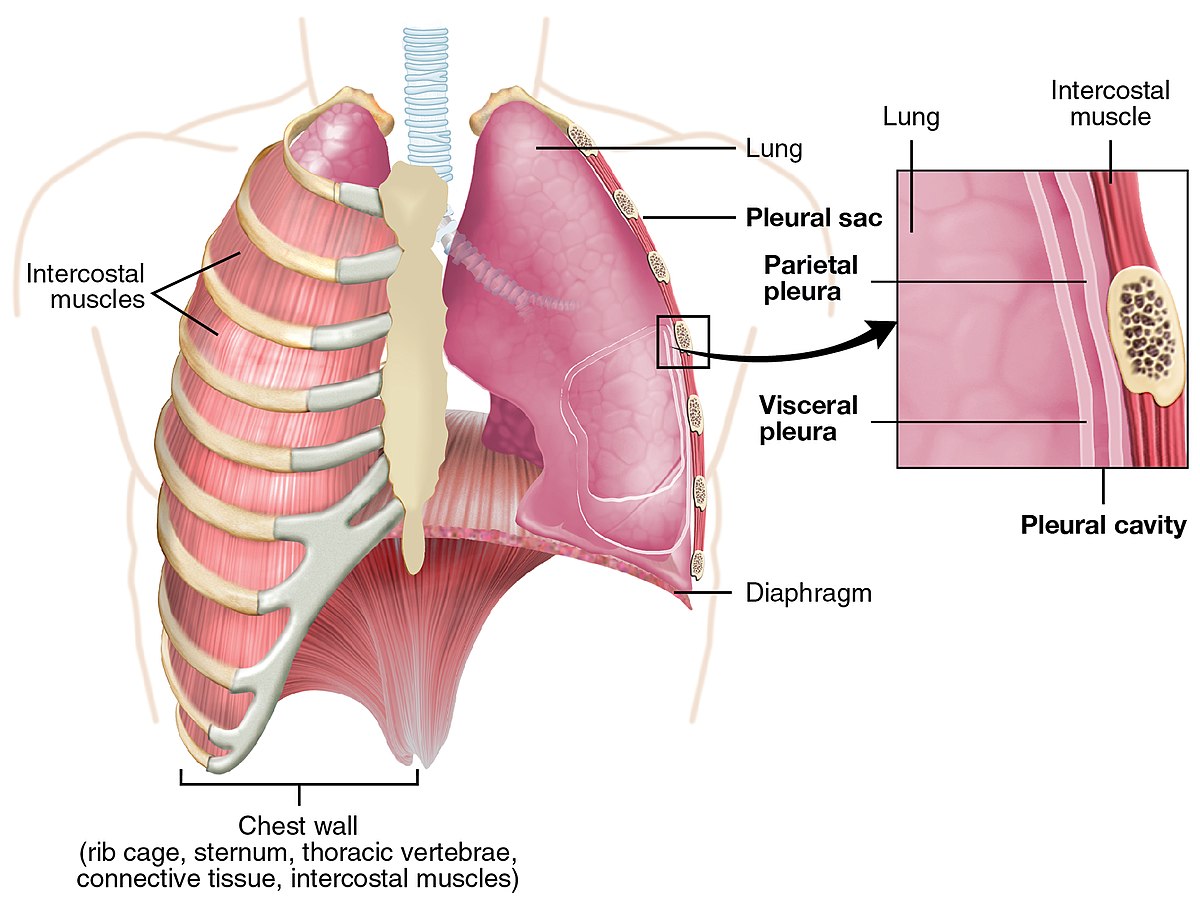

Анатомия межплеврального пространства